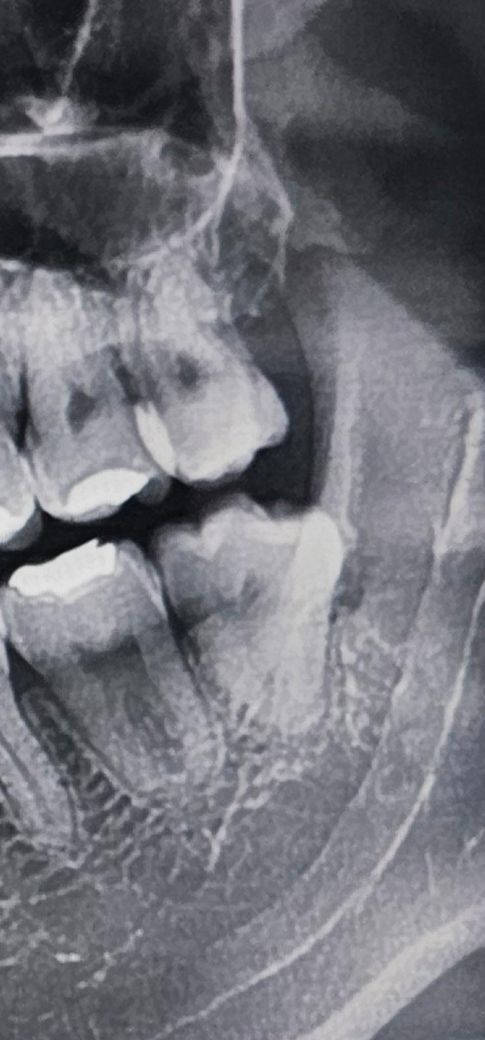

사랑니 발치 난이도 좀 봐주세요 슨생님들

1. 전체적인 발치 난이도 좀 알려주세요

3. 상악 사랑니랑 옆 어금니 치조골이 없어보이는데

사랑니 발치해도 어금니에 영향이 없나요?

난이도가 높은 사랑니 발치는 아니지만 구강악안면외과 전문의가 원장인 병원을 가시면 그만큼 더 수월하게 발치는 가능하실거 같습니다. 발치후 3달 정도가 지나면 인접치의 치조골도 어느정도 차오르니 너무 걱정안하셔도 될거 같습니다.

사진상으로 보면 사랑니 뿌리도 모여 잇는 형태로 입만 잘벌릴수 잇다면 난이도가 높아 보이진 않아 보입니다.

사랑니가 똑바로 나와 있고 뿌리가 모아져 있기 때문에 발치를 하는데 크게 어려움은 없을것으로 생각됩니다.

그렇게 어렵진 않을 것 같습니다. 뿌리도 잘 모여있고, 맹출 정도도 나쁘지 않고요.

이정도면 일반 동네 치과 아무데나 가셔도 됩니다.